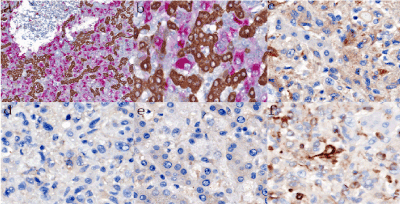

Immunohistochemical staining (Table 1) revealed that the spindle-epithelioid neoplastic cells were strongly and diffusely positive for HMB45 (Figure 3A and 3B) and weakly positive for Melan-A (Figure 3C) but were negative for hepatocyte (Hep Par-1), CK, S100 (Figure 3D), ALK (Figure 3E), CD21, CD23, CD68 and TFE3. Vimetin was positive in spindle-epithelioid neoplastic cells (Figure 3F). Adipocytes and blood vessels within the tumor were positive for S-100 and CD34, respectively. Ki-67 index was low (~3%).

Figure 3. Immunostaining of the hepatic AML

a-b Double immunostaining for hepatocyte (brown) and HMB45 (red). The hepatocytes were stained brown, while the epithelioid tumor cells were stained red. Sinusoidal infiltration by the epithelioid tumor cells was highlighted (a, × 100; b, × 400). c The epithelioid tumor cells were weakly positive for Melan-A (× 400). d The epithelioid tumor cells were negative for S100 (× 400). e The epithelioid cells were negative for ALK (× 400). f Vimentin was positive in the epithelioid cells (× 400).

Besides, double-staining of Hep Par-1 and HMB45 clearly highlighted that the tumor cells grow along the hepatic sinusoids (Figure 3A and 3B); this kind of growth pattern was found nearly in the whole tumor, which showed a prominent invasive growth pattern.